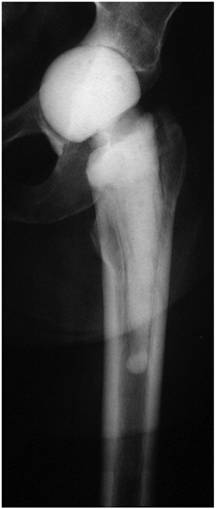

Depending on the particular cause, treatment options may strongly vary. In case of patient incompliance or inability to put partial weight bearing on the operated extremity, the patient should be rather considered as a candidate for a resection arthroplasty and not for a spacer implantation. For prevention of any spacer dislocation due to an insufficient fixation technique onto the proximal femur, a simple “press fit” method should be avoided (Figure 1). Alternatively, a partial (Figure 2) or normal cementation of the spacer into the femoral canal provides the advantage of rotational and axial stability [3]. A normal cementation has the disadvantage in comparison with the partial cementation that all cement debris have to be removed from the femoral canal during the later prosthesis reimplantation, and that during removal of the prosthesis stem osseous defects might occur. Recently, the “glove”-technique has been described as new method for femoral fixation of hip spacers [3]. This method provides a stable fixation onto the proximal femur at facilitating the spacer's explantation since the spacer can be removed at one piece and there is no need for removal of any cement debris compared with other normal cementation techniques.

Figure 2

Articulating hip spacer in situ, the partial cementation of the spacer onto the proximal femur provides a rotational stability; at prosthesis reimplantation, the spacer can be removed at one piece, leaving no cement particles in the femoral canal.